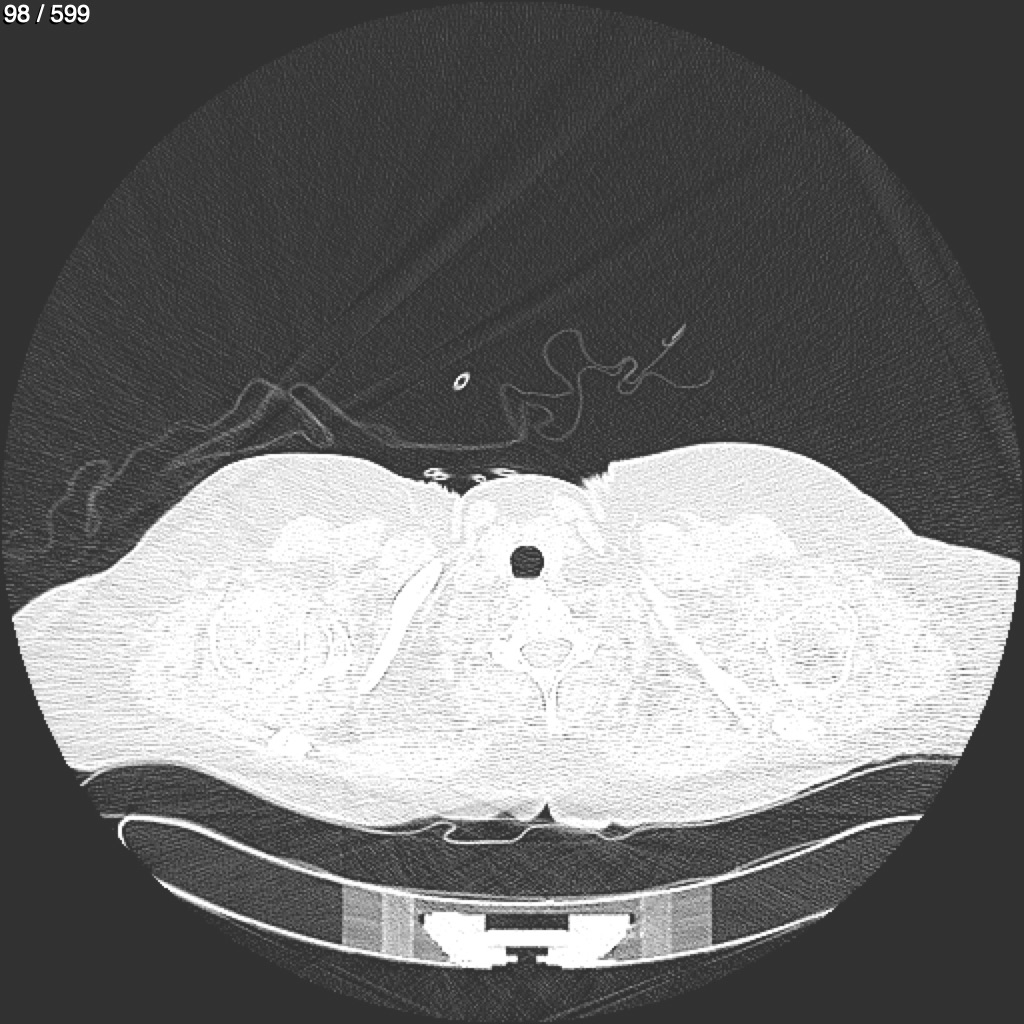

Home G​l​o​r​i​a​ ​G​l​a​d​y​s​ ​B​e​a​s​l​e​y​ ​-​ ​T​ó​r​a​x​ ​T​o​r​a​x​_​S​i​m​p​l​e​ ​(​A​d​u​l​t​o​)